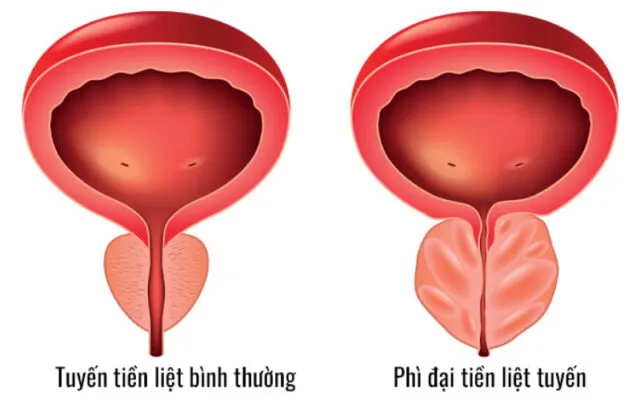

U phì đại tuyến tiền liệt: Cách điều trị

U phì đại tuyến tiền liệt là một vấn đề sức khỏe phổ biến ở...

U tuyến tiền liệt là gì?

Sức khỏe nam giới, đặc biệt là khi bước vào độ tuổi trung niên, luôn...